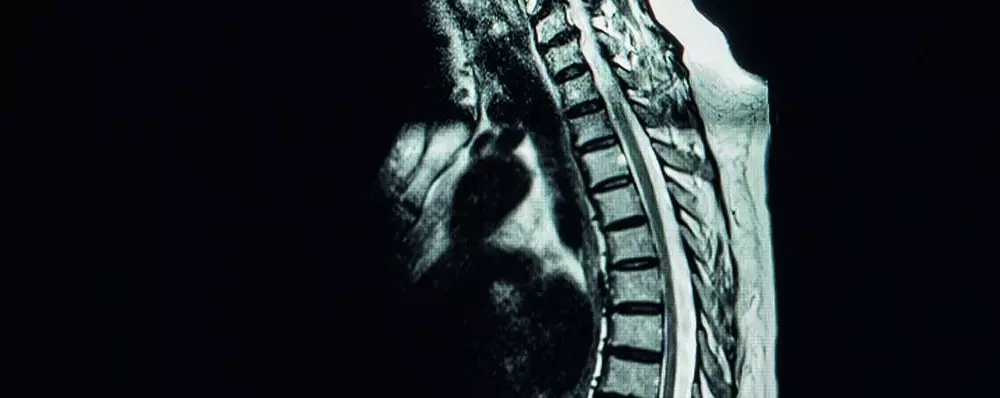

- urazach splotu ramiennego,